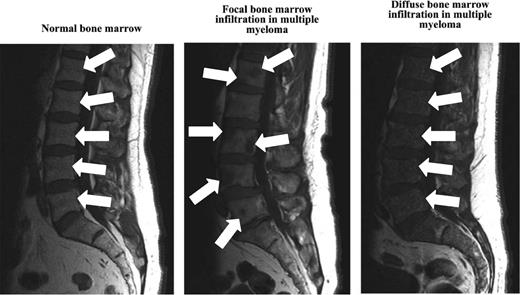

New imaging techniques allow detection of myeloma manifestations earlier than conventional radiography.49 Although CT and skeletal survey detect lytic lesions in the bone as a secondary event, MRI is able to assess the disease in the BM itself independently from the growth pattern and therefore can provide information on the actual tumor burden. In addition to those functional techniques such as PET/CT or PET/MRI, dynamic contrast-enhanced MRI and diffusion weighted imaging MRI comprise the possibility of gaining information regarding disease activity.49 Interestingly, Hillengass et al reported recently that 30% of patients with SMM have BM infiltration patterns similar to multiple myeloma when using whole-body MRI (Figure 2, Table 2).49,53 Indeed, based on 149 SMM patients followed up to 60 months, the investigators found SMM patients with > 1 focal BM lesion to have a significantly (P < .001) shorter time (median time to progression: 13 months vs not reached) to develop multiple myeloma compared with SMM patients with ≤1 focal BM lesion.47

MRI of the BM in healthy controls and in patients with multiple myeloma.